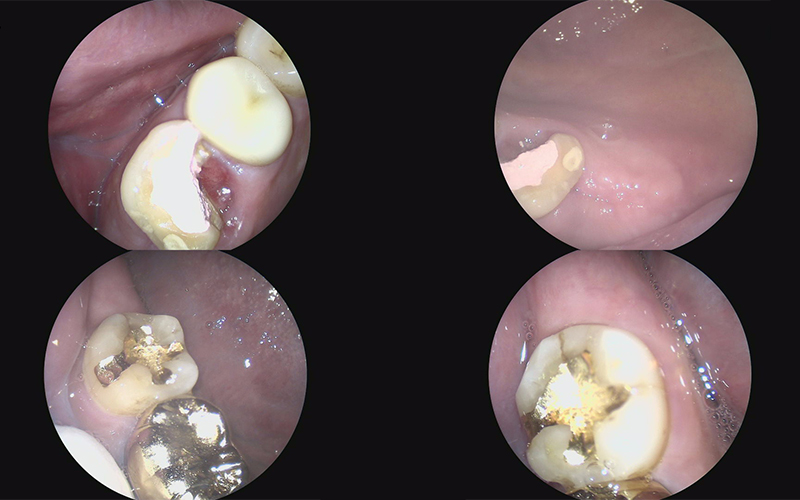

We also took an intraoral camera image

to carefully check the condition inside the mouth,

and explained it to the patient while showing it to them.